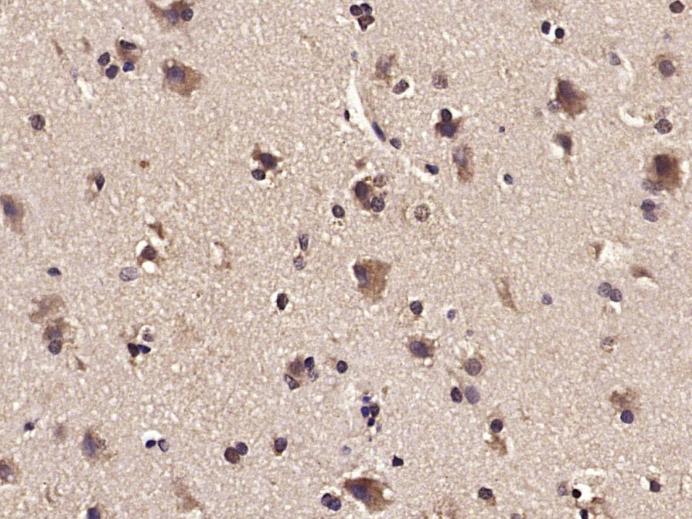

Primary: Anti-PIK3R2 (bs-4160R) at 1/1000 dilution

| {IHC-P} | {1:100-500} |